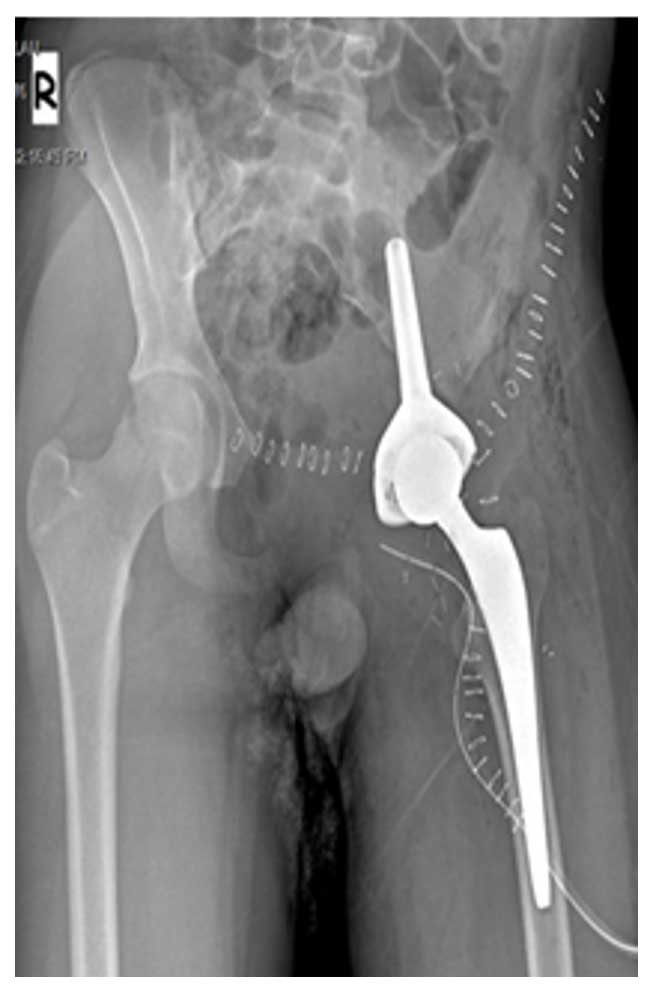

Ameliyat Sonrası: İnternal hemipelvektomi sonrası Lumic protez uygulanımı görülmekte.